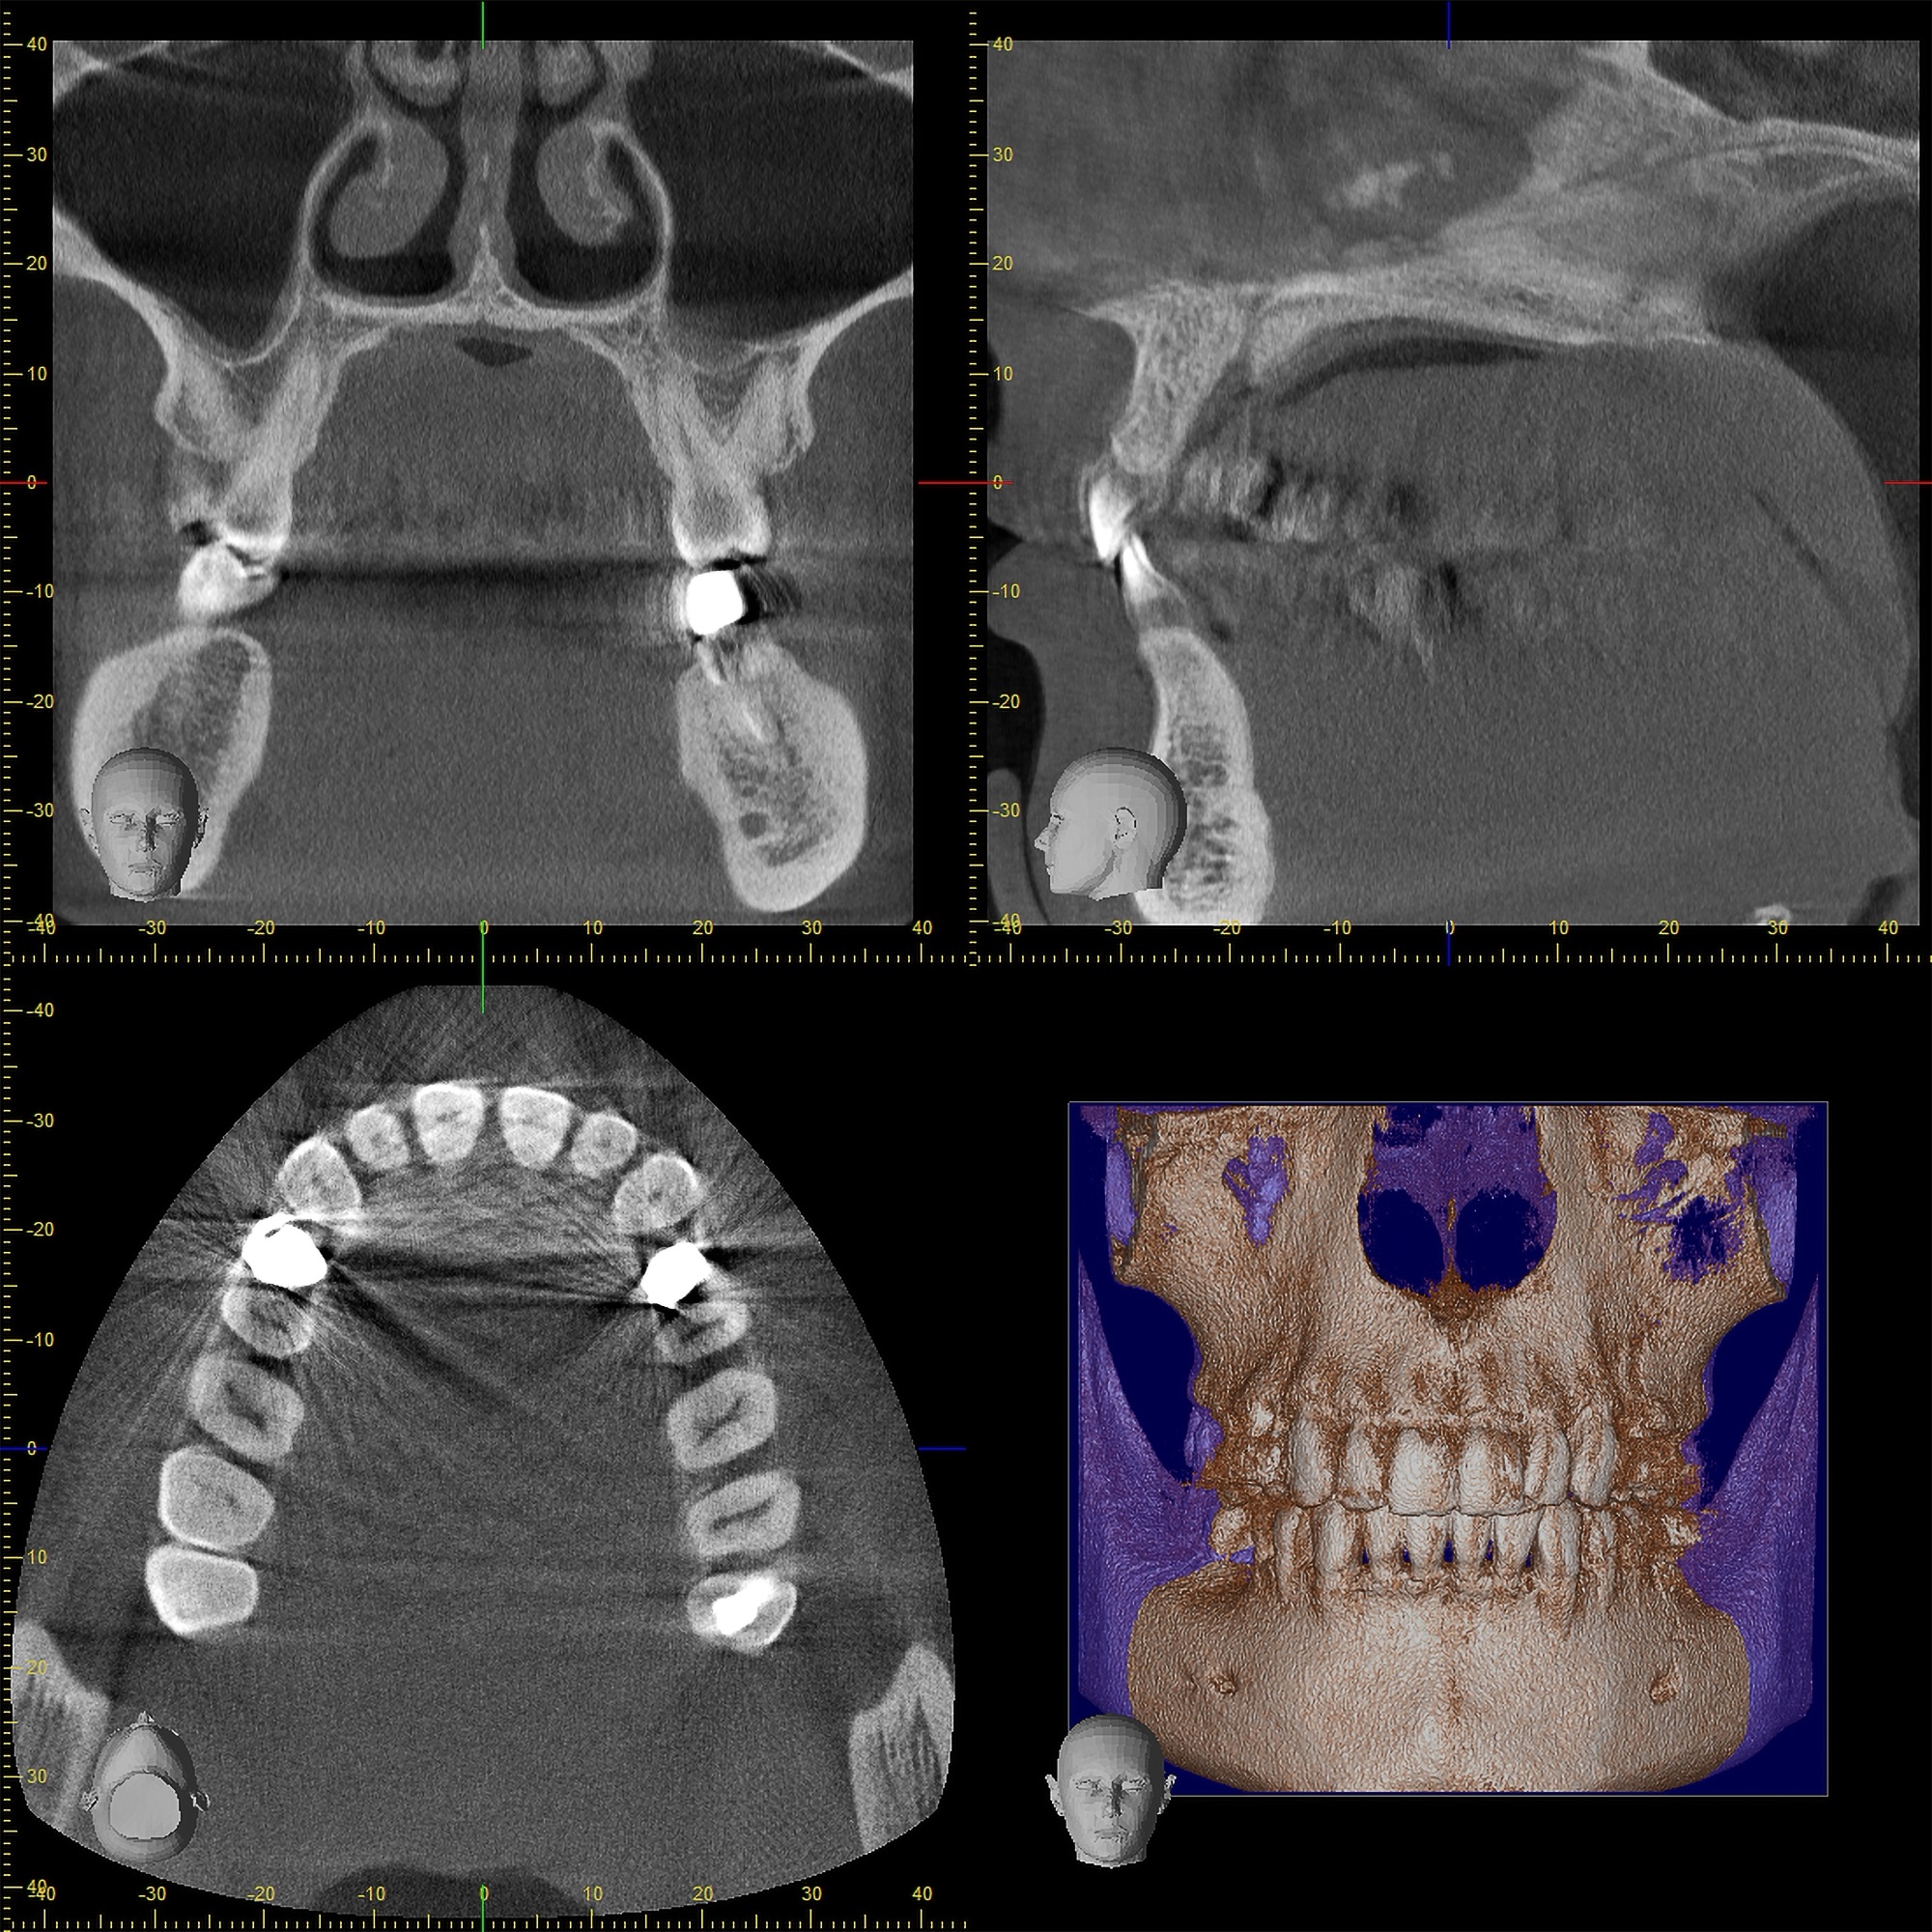

6. 大学病院レベルの「最新デジタル設備」

精密な診断と低侵襲(体に負担の少ない)治療のため、最新設備を惜しみなく導入しています。

• 歯科用CT: 骨の状態を3Dで正確に把握。